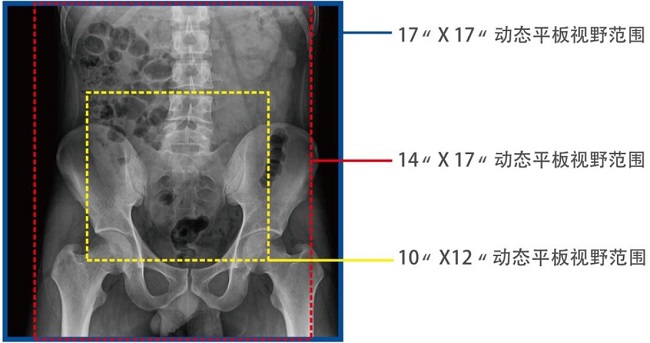

一、大視野無遺漏

17*17英寸的超高清像素動態(tài)平板探測器,更大的視野范圍,能對胸部腹部等部位實現(xiàn)大范圍全覆蓋,動靜態(tài)之間無感切換。透視檢查無須對患者重新定位便可觀察到足夠大的人體器官組織,避免漏診誤診。

大尺寸動態(tài)平板技術,覆蓋檢查面積范圍廣,輕松實現(xiàn)胃十二指腸等大面積造影,無需移動即可觀看整個動態(tài)過程,避免噪點對圖像的影響。